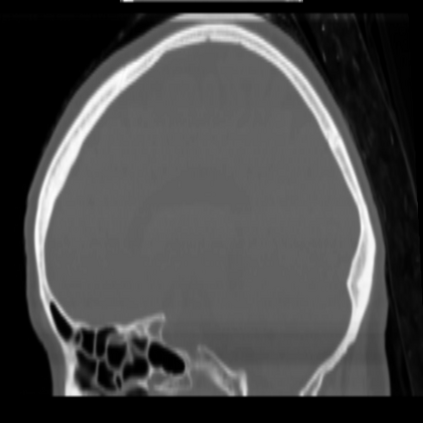

CT reconstruction provides radiologists with images for diagnosis and treatment, yet current deep learning methods are typically limited to specific anatomies and datasets, hindering generalization ability to unseen anatomies and lesions. To address this, we introduce the Multi-Organ medical image REconstruction (MORE) dataset, comprising CT scans across 9 diverse anatomies with 15 lesion types. This dataset serves two key purposes: (1) enabling robust training of deep learning models on extensive, heterogeneous data, and (2) facilitating rigorous evaluation of model generalization for CT reconstruction. We further establish a strong baseline solution that outperforms prior approaches under these challenging conditions. Our results demonstrate that: (1) a comprehensive dataset helps improve the generalization capability of models, and (2) optimization-based methods offer enhanced robustness for unseen anatomies. The MORE dataset is freely accessible under CC-BY-NC 4.0 at our project page https://more-med.github.io/